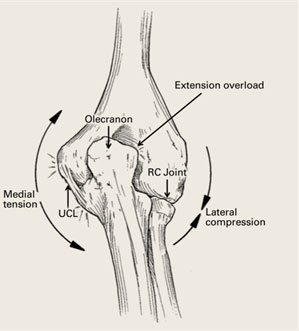

- As the elbow is forced into extension at the end of throwing cycle, there is a shearing force across the back of the elbow at the olecranon. This repetitive loading leads to compression in the posterior elbow.

- In the adolescent overhead athlete these forces lead to separation of the olecranon ossification center and if left untreated this can develop into an unfused olecranon apophysis and ultimately a symptomatic nonunion

- In the skeletally mature (adult) this can result in formation of bone spurs (osteophytes) and pain along the posterior medial aspect of the elbow known as valgus extension overload.

- In both adolescents and adults, this repetitive trauma can result in stress reactions or even stress fractures into the olecranon